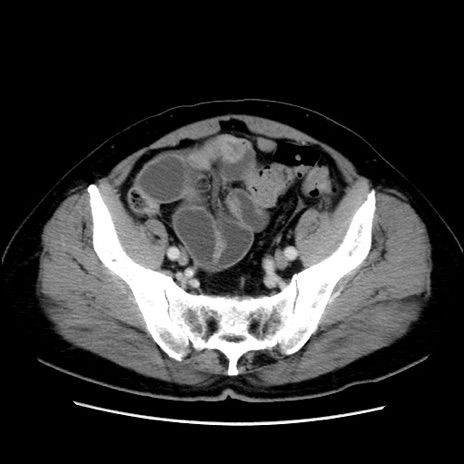

冠状断像